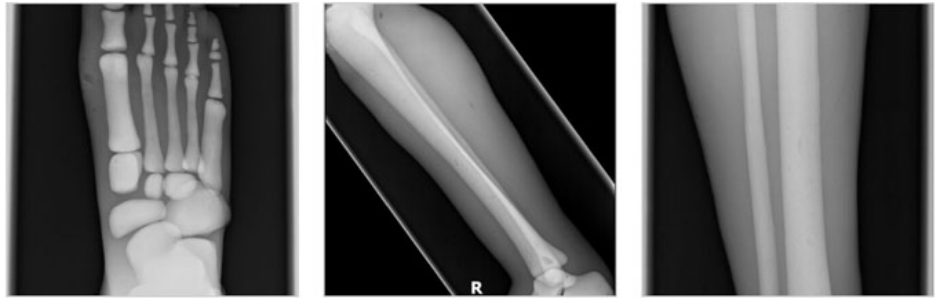

成人腿部模體,用于 X 射線(xiàn) CT 和超聲波的成人腿部(肌肉)模型是一種基于人類(lèi)男性腿部平均解剖結(jié)構(gòu)設(shè)計(jì)的逼真模型。它具有所有基本的骨骼和

軟組織特征,使其成為學(xué)習(xí)、研究和測(cè)試醫(yī)學(xué)成像設(shè)備的理想工具。 模體可用于研究不同方向和定位技術(shù)的多種診斷性 X 射線(xiàn) CT 和超聲程序。根據(jù)

要求,該產(chǎn)品可以根據(jù)不同的病理進(jìn)行定制,也可以用于特定的培訓(xùn)應(yīng)用。 模體尺寸:965.2 x 254 x 177.8 毫米,重量:12kg(約)